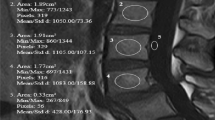

Along with the standard L1/2 vBMD measurement, we measured regional Tb-vBMD that was defined as the average vBMD of the upper and lower vertebral trabecular bones in the same method as the standard L1/2 measurement recommended for osteoporosis screening by 3D QCT (Fig. 1a) [19]. If there were any apparent sclerotic regions, which lead to inaccurate measurement of trabecular vBMD in the vertebra, the regions were excluded from the area of interest (AOI) [20,21,22]. In cases where sclerosis was too diffuse to be excluded, the vertebra was excluded from analysis. All CTs were conducted with the patient in the supine position.

Tb-vBMD and EP-vBMD measurements a Tb-vBMD measurement of L4 vertebra, b EP-vBMD measurement of L4 lower endplate, c EP-vBMD measurement of L5 upper endplate. Upper row: axial images. Middle row: sagittal reconstruction images. Lower row: coronal reconstruction images. Circle and boxes represent for the area of interest

EP-vBMD was defined as the average of the upper and lower endplate volumetric BMDs measured in cortical and trabecular bone included in a 5-mm AOI beneath the cage contact surfaces (Fig. 1b, c). First, the position of the cage was checked with postoperative CT and radiographs. The AOI was set to include as much cage contact surface of each endplate as possible. Special care was taken not to let the AOI exceed the outer cortical margin of the vertebra and endplate to avoid inclusion of any outer- or inter-vertebral spaces. Unlike the Tb-vBMD measurement, all sclerotic regions and endplate defects were included in the AOI for EP-vBMD, if these were located in the cage contact surfaces.